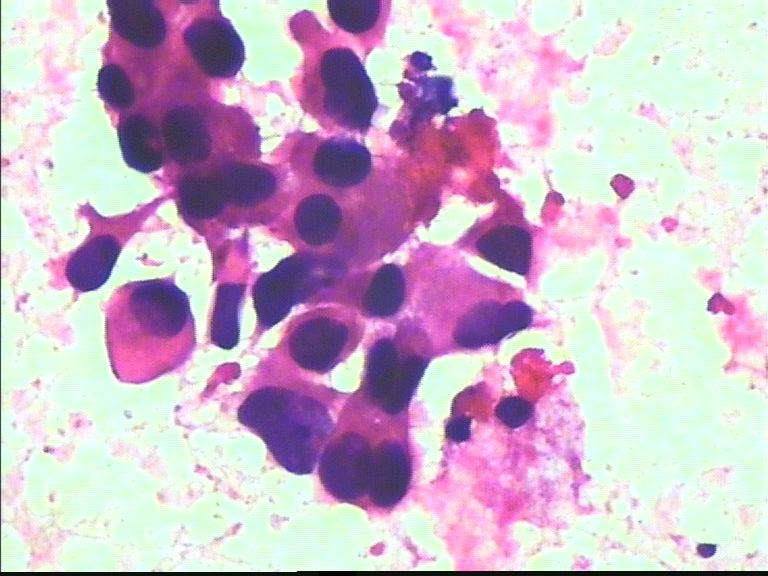

38岁 乳腺肿瘤 女

• 38岁 乳腺肿瘤 女图2

图2

恶性肿瘤细胞

导管癌

乳腺导管癌

我试着说一下,不对的地方请其他老师修正。良恶性细胞鉴别主要还是观察细胞核的形态和大小、染色质颗粒是否细腻均匀,核膜是否光滑增厚等,还有涂片的背景是否有坏死等。这个病例就是一个很明显的恶性病例。形态学的东西讲究的就是多看多比较,慢慢就能掌握的。不急哦!

非常明显的恶性肿瘤细胞,倾向浸润性导管癌。细胞异型性大,非常弥散,未见肌上皮细胞。

润性导管癌,细胞大小不一、异形明显、粘附性差,尤其是在同一堆细胞内。